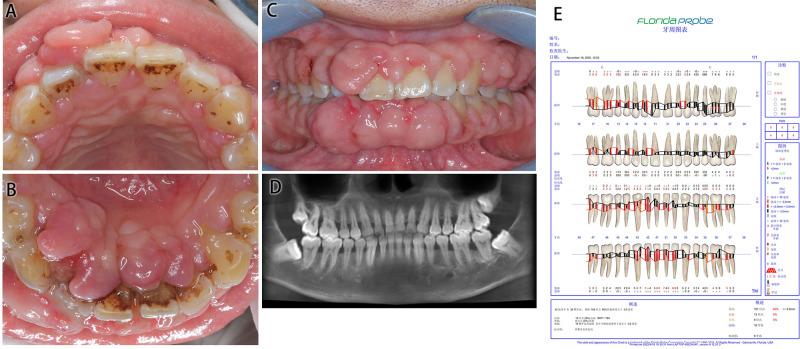

Drug-induced gingival overgrowth is common but neglected in patients with systemic disease medications until it seriously affects the quality of life.

Initial periodontal treatment, combined with water laser surgery, was performed sequentially in two cases.

The therapeutic effect was good, and there was no recurrence along with good oral hygiene.